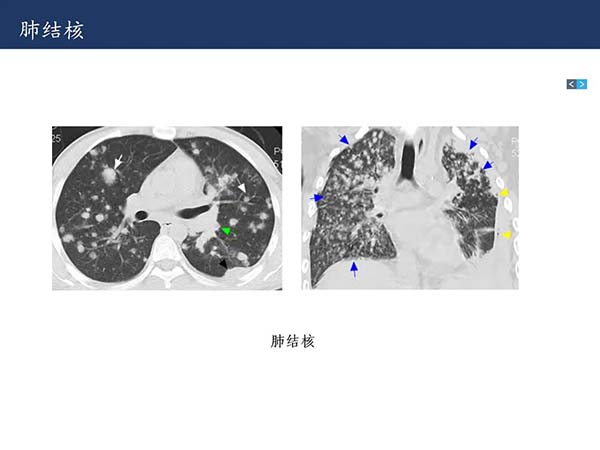

【杨柳科普】肺上皮样血管内皮瘤的影像表现